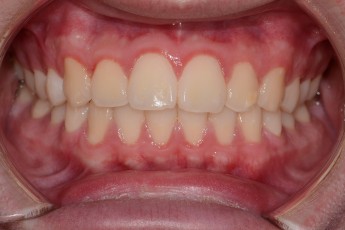

Before

After